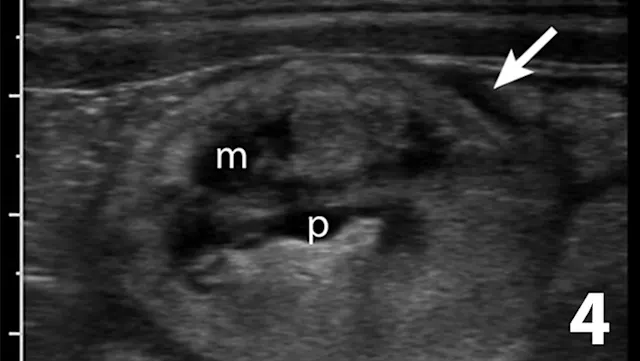

Similar to survey radiography, ultrasonography can document the number, size, shape, and location of the kidneys as well as the presence of mineralized tissue and nephroliths. In contrast to radiography, abdominal fluid or lack of abdominal fat does not limit the utility of ultrasound. The major advantage of ultrasound for evaluating kidney disease is its ability to assess the internal renal architecture and perirenal tissues. Both focal and diffuse lesions are recognized. Focal lesions may be solid, either homogenous or heterogenous, or fluid in nature. Diffuse lesions (Figures 4-8) may uniformly affect the parenchyma or be heterogenous. The renal cortex, medulla, or both regions may be affected depending on the disease process.